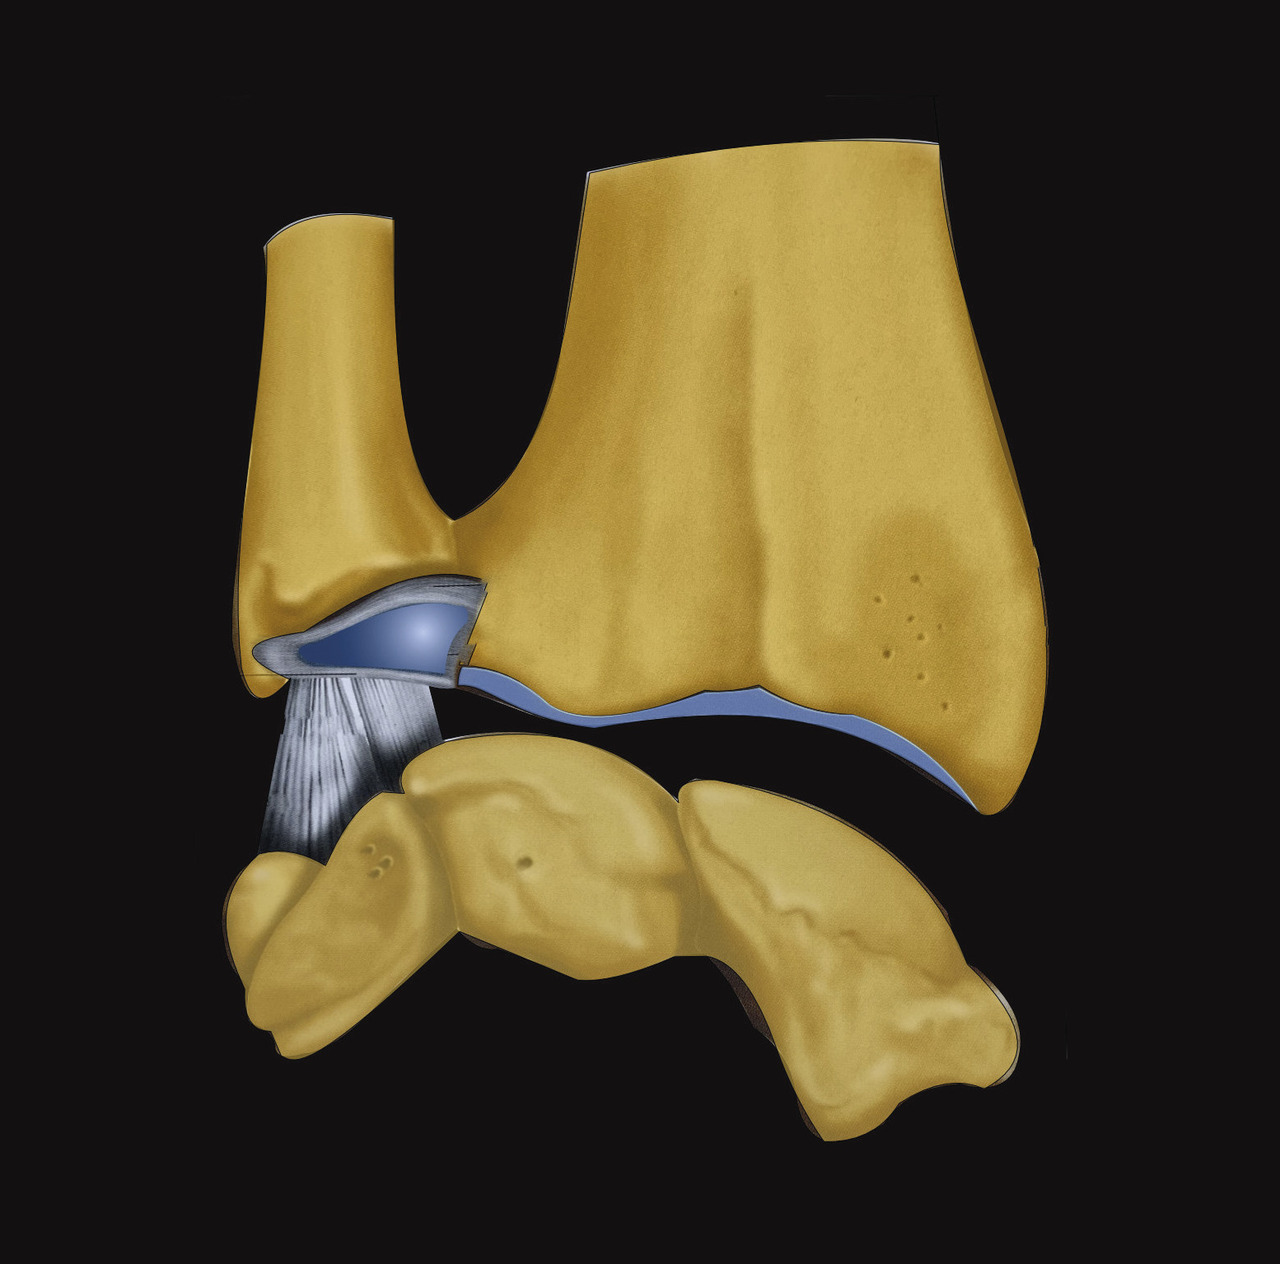

Enfin, le complexe ligament triangulaire prolonge la surface articulaire distale du radius sur son versant médial. Il s’agit d’une structure ligamentaire tendue du versant médial et distal de l’extrémité inférieure du radius, sur le pourtour de l’incisure ulnaire jusqu’à la base de l’apophyse styloïde de l’ulna (fig. 5). Ainsi, l’extrémité distale du radius, l’articulation radio-­ulnaire distale, le complexe ligamentaire triangulaire et l’extrémité distale de l’ulna constituent une entité anatomofonctionnelle continue, composite et indissociable. Les lésions associées aux fractures de l’extrémité inférieure du radius, comme les fractures de la styloïde ulnaire ou les lésions ligamentaires du complexe triangulaire, appartiennent donc au même spectre lésionnel. On s’attachera par conséquent à rechercher systématiquement une participation articulaire aux lésions fracturaires et des lésions ligamentaires associées.